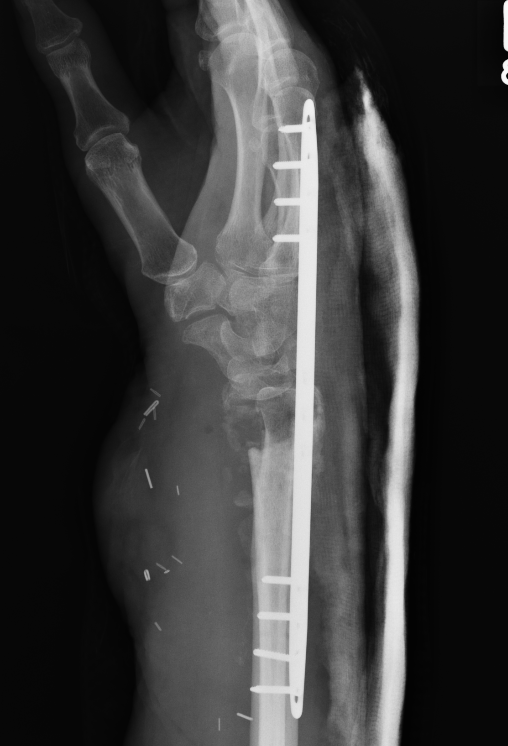

Undisplaced wrist fracture

- interrupts blood supply at a watershed area

- between 3 weeks and 3 months post injry